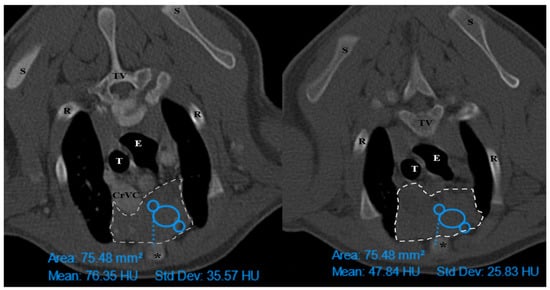

The thymus was evaluated in the first step to determine whether it was visible or not. Non-visible thymus was that with complete degeneration seen with fat attenuation and not distinguishable from mediastinal fat. After that, a grading system for thymic tissue appearance was used based on its predominant component (grade 0: totally fatty replacement of the thymus (non-visible) and could not differentiate from mediastinal fat; grade 1: more than 50% fatty replacement of the thymus; grade 2: more than 50% soft tissue component in the thymus; grade 3: totally soft tissue component in the thymus. After grading the thymus, the attenuation (CT number) of thymic tissue in plain and contrast-enhanced images was measured. For this purpose, a round-shaped region of interest (ROI) with a surface equal to 75 mm2 was considered in the widest part of the organ for large thymus (Figure 1) and a smaller ROI for small thymus. Then pre- and post-contrast Hounsfield Units (HU) were compared for each patient individually and also between groups for evaluating the pattern of attenuation alteration and enhancement alteration.

Figure 1. Illustration of density measurement of thymus in plain (right) and post-contrast (left) CT scan examination in a ROI equal to 75 mm2. These figures belong to a four-month mixed-breed male puppy. The grey dash lines show the grade3 rectangular-shaped midline-position thymus. S: scapula, TV: thoracic vertebra, R: rib, E: esophagus (which is dilated due to general anesthesia), T: trachea, CrVC: cranial vena cava, and asterisk: second sternebra.